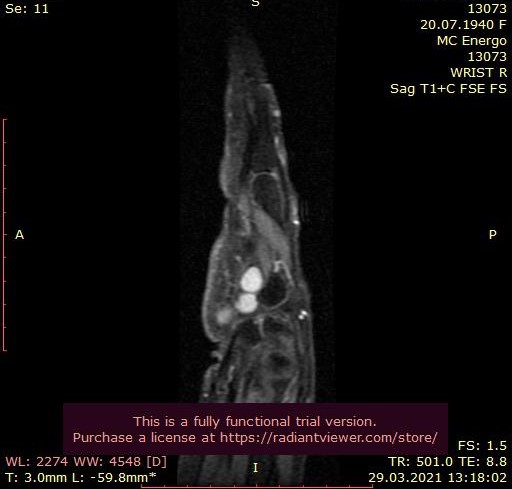

Специалисты Центра Алмазова приняли решение о госпитализации пациентки в стационар РНХИ им. проф. А. Л. Поленова. В ходе обследования медиками был выявлен редкий вид туннельной невропатии — сдавление локтевого нерва в канале Гюйона. Помимо этого, по данным УЗ-исследования выявлено образование канала Гюйона, природу которого можно было установить исключительно интраоперационно. Был поставлен точный диагноз «объемное образование локтевого нерва с выпадением функций правой кисти».

В результате оперативного вмешательства, выполненного на высочайшем уровне, утраченные функции полностью восстановились, была достигнута декомпрессия локтевого нерва с сохранением его целостности. Удалось установить доброкачественный характер образования, деформировавшего лучезапястный сустав, связочный аппарат ладонной поверхности правой кисти и сосудисто-нервные структуры, которое было удалено тотально.